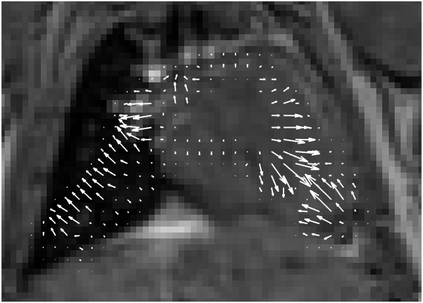

Various imaging modalities allow for time-dependent image reconstructions from measurements where its acquisition also has a time-dependent nature. Magnetic particle imaging (MPI) falls into this class of imaging modalities and it thus also provides a dynamic inverse problem. Without proper consideration of the dynamic behavior, motion artifacts in the reconstruction become an issue. More sophisticated methods need to be developed and applied to the reconstruction of the time-dependent sequences of images. In this context, we investigate the incorporation of motion priors in terms of certain flow-parameter-dependent PDEs in the reconstruction process of time-dependent 3D images in magnetic particle imaging. The present work comprises the method development for a general 3D+time setting for time-dependent linear forward operators, analytical investigation of necessary properties in the MPI forward operator, modeling aspects in dynamic MPI, and extensive numerical experiments on 3D+time imaging including simulated data as well as measurements from a rotation phantom and in-vivo data from a mouse.